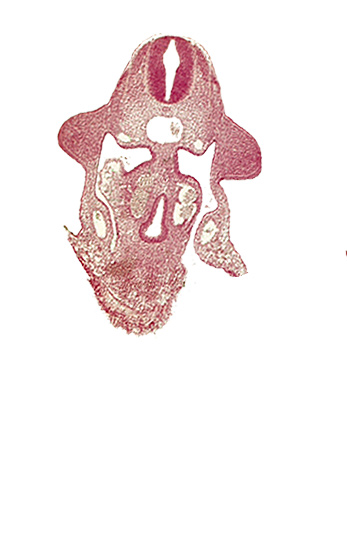

Carnegie Embryo #836 | Location: 09-02-02

Keywords: amnion attachment, aorta, apical ectodermal ridge, coelomic cavity, duodenum primordium, hepatic antrum, notochord, postcardinal vein, sulcus limitans, upper limb bud

Source: The Virtual Human Embryo.